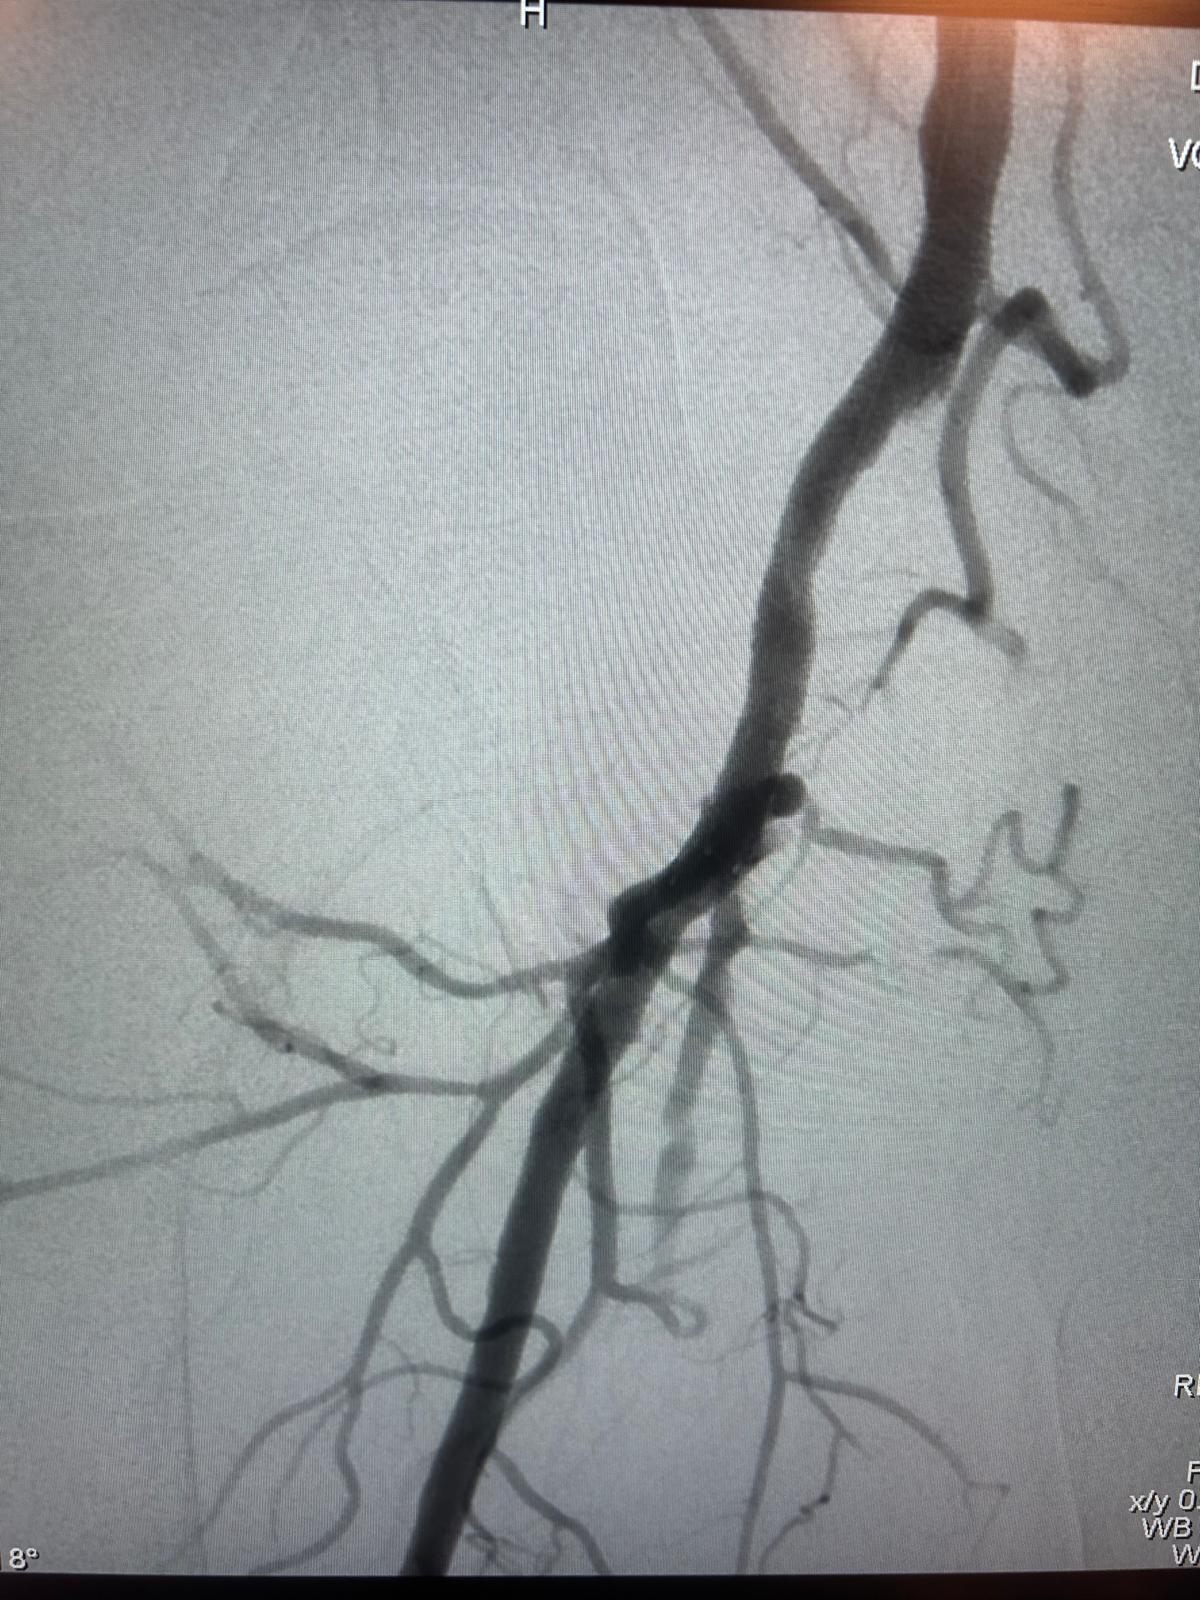

Imagerie pré-opératoire

Angio-TDM montrant une occlusion longue, intra-stent, hypodense, à l'origine de l'artère fémorale superficielle droite, mal compensée par la collatéralité fémorale profonde.

En distalité, belle artère tibiale postérieure unique assurant la vascularisation du pied.

Résultat

Excellent résultat anatomique immédiat au contrôle artériographique per-opératoire.

Respect de la perméabilité de l'ostium de l'artère fémorale profonde et de ses collatérales au niveau de la jonction fémoro-poplitée.

Aucune embolisation distale per-opératoire constatée au niveau des artères de jambe et du pied.

Très bonne revascularisation clinique du pied et excellent pouls tibial postérieur droit.